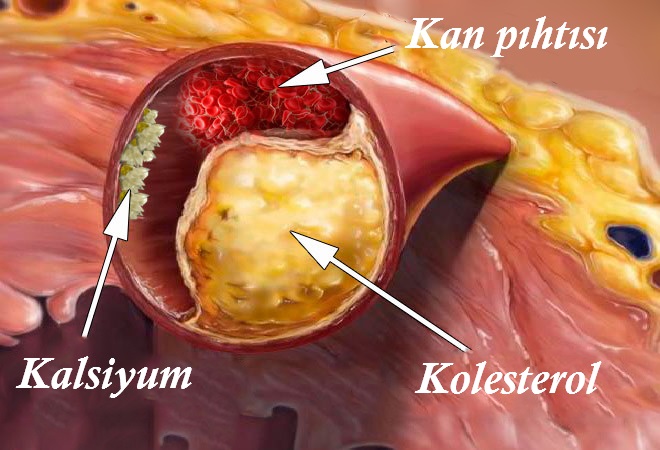

Svi znamo koliko je holesterol opasan. Blokira vene, sužava hodnike i na taj način sprečava protok krvi. Ali nije holesterol jedino što uzrokuje ovo.

Tačno je. Naslage holesterola ili „aterosklerozne naslage“ predstavljaju 65-70% uzroka vaskularnih poremećaja.

Svaka osoba nakupi do 5 kilograma naslaga holesterola u telu do 50. godine. Skladišteni holesterol sužava vaskularne lumene (prazan prostor unutar vena kojima krv teče) za 4-5 puta.

Pokušajte da zamislite. Ako kažemo da je vaskularna širina otprilike široka kao prst, unutar vena koje su blokirane sa 5 kilograma holesterola širina praznog prostora kroz koji krv može da teče je oko širine 4 šibice.

Ove naslage možda ne nose vitalni rizik, ali kvaliteta života se smanjuje, povećava se krvni pritisak, pojavljuju se bolovi u glavi, bolovi u leđima i utrnulost. Skuta koja se nakuplja unutar vena mnogo je opasnija.

Skuta koja se nakuplja unutar vena toliko je lakša, da iznosi “samo” 800 grama do 1 kg. Ali zbog njene nestabilne strukture, vrlo je opasna. Tromb (skuta koja blokira venu) može da se odvoji od venskog zida u koji je zaglavila i svakog trenutka početi da traži žrtvu.

Veliki komadi tromba mogu u potpunosti da blokiraju venu svojih žrtava. U tom slučaju tkivo ne može da dobije dovoljno krvi.

Napad ishemije je začepljenje moždanih vena. Srčani udar je blokiranje srčanih vena. Zbog toga se razvija ishemija jetre, zatajenja pluća i zatajenja bubrega. Hemoroidi su ishemija koja se pojavi na rubu rektuma. Blokiranje kapilara na nogama može da rezultira nekrozom (gangrenom).

Prehrambeni dodaci i hemijski ostaci lekova uzrokuju nakupljanje kalcijeve soli u venama. Osoba nakupi 300-400 grama soli tokom 50 godina života. Kalcijeva sol se najviše akumulira u mozgu.

Opasna je zbog svoje kristalne strukture. Sužava vene i ako vene imaju grčeve uslijed stresa, fizičkog kretanja ili promene zraka, oštri kristalni rubovi mogu da probuše venu. Bušenje moždanih vena poznato je kao hemoragični moždani udar.